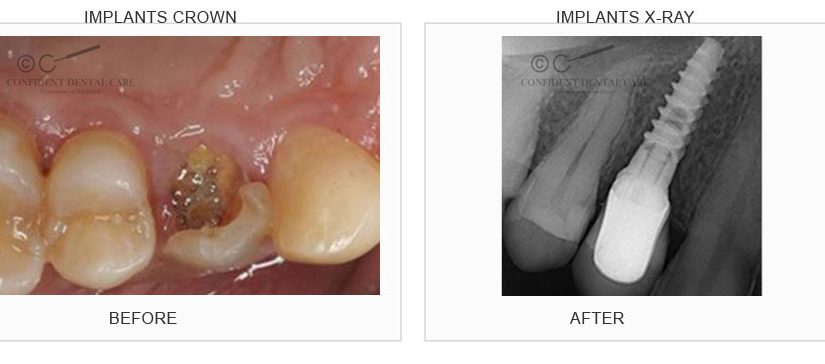

Implant Crown